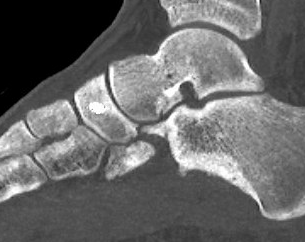

CT

Minimally displaced navicular stress fracture

Displaced navicular stress fracture